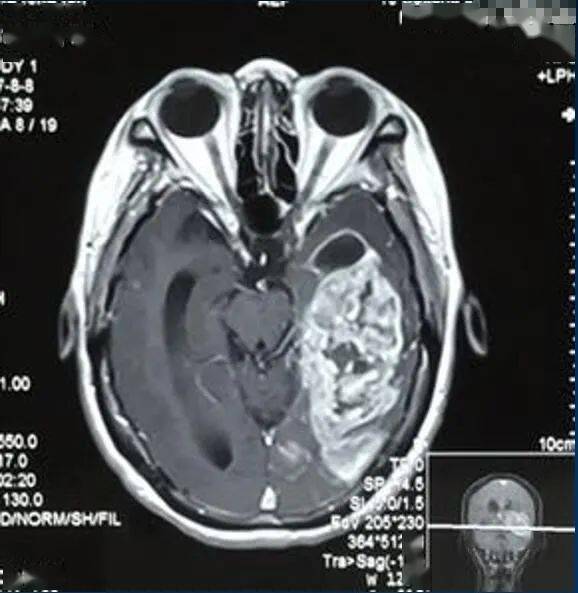

此外还有一些伴随症状也需要我们的注意:颈部出现肿块、质地较硬可能是肿瘤转移的迹象;耳朵疼痛可能与咽喉肿瘤刺激周围神经有关;单侧鼻塞、鼻涕带血可能是鼻咽部肿瘤的表现。这些症状的出现都提示我们可能患有咽喉疾病。如果这些症状持续三周以上没有缓解的迹象或者症状进行性加重,一定要及时就医排查。早期喉癌(如声门型)预后较好,但其他类型的肿瘤症状可能较为隐匿,容易被忽视。为了健康着想,出现上述症状时建议及时就医进行喉镜检查或颈部影像学检查,明确诊断后接受针对性的治疗(如手术、放疗等)。